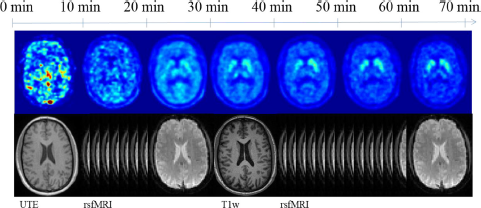

PET scanning lasted 70 min and started simultaneously with an intravenous injection of 150 MBq of [18F]-FDOPA. PET data were reconstructed using ordered subset expectation maximization (OSEM) (21 subsets, 3 iterations) with a voxel size of 1.7 × 1.7 × 2 mm3 and corrected for attenuation and scatter based on anatomical MR information. 30 dynamic frames were created (1 × 30 s, 10 × 15 s, 3 × 20 s, 2 × 60 s, 2 × 120 s, 12 × 300 s). The MRI sequences were acquired simultaneously with PET. Resting-state functional MRI data were obtained by three separate sequences: whole-brain, focus on basal ganglia and orbitofrontal cortex, and focus on medial temporal lobe. T1-weighted anatomical data were also acquired.

The protocol adopted at Munich is described in Table 1 and illustrated in Fig. 2.

Fig. 2 Method and scanning protocol followed by the Munich group in the search of a biomarker.

PET data were motion corrected by realigning all frames (starting from 5 min) to the last PET frame (65–70 min), and then applying the transformation matrix for the last frame to all the early frames. A graphical Patlak analysis over the time frames from 20 to 60 min was conducted obtaining whole-brain kinetic parametric maps. From Patlak analysis the dopamine synthesis capacity can be measured through the index of the influx Kc. The simplified reference tissue model [Reference Lammertsma and Hume28], with the cerebellum as reference, was adopted to circumvent the necessity of arterial blood sampling. To correct for FDOPA metabolites the signal from the cerebellum was taken as a surrogate of the metabolite measurement from the plasma [Reference Kumakura, Vernaleken, Gründer, Bartenstein, Gjedde and Cumming29].